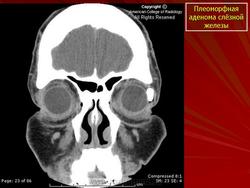

При рентгенографии выявляют увеличение полости орбиты вследствие истончения и смещения кверху и кнаружи ее стенки в области слезной ямки. Ультразвуковое сканирование позволяет определить тень плотной опухоли, окруженной капсулой, и деформацию глаза. При компьютерной томографии опухоль визуализируется более четко, можно проследить целость капсулы, распространенность опухоли в орбите, состояние ее прилежащих костных стенок. Лечение только хирургическое. Прогноз для жизни и зрения в большинстве случаев благоприятный, но пациента следует предупредить о возможности рецидива, который может возникнуть через 3—45 лет. Приблизительно у 57 % больных при первом же рецидиве обнаруживают элементы озлокачествления. Опасность злокачественного перерождения плеоморфной аденомы возрастает по мере увеличения периода ремиссии.